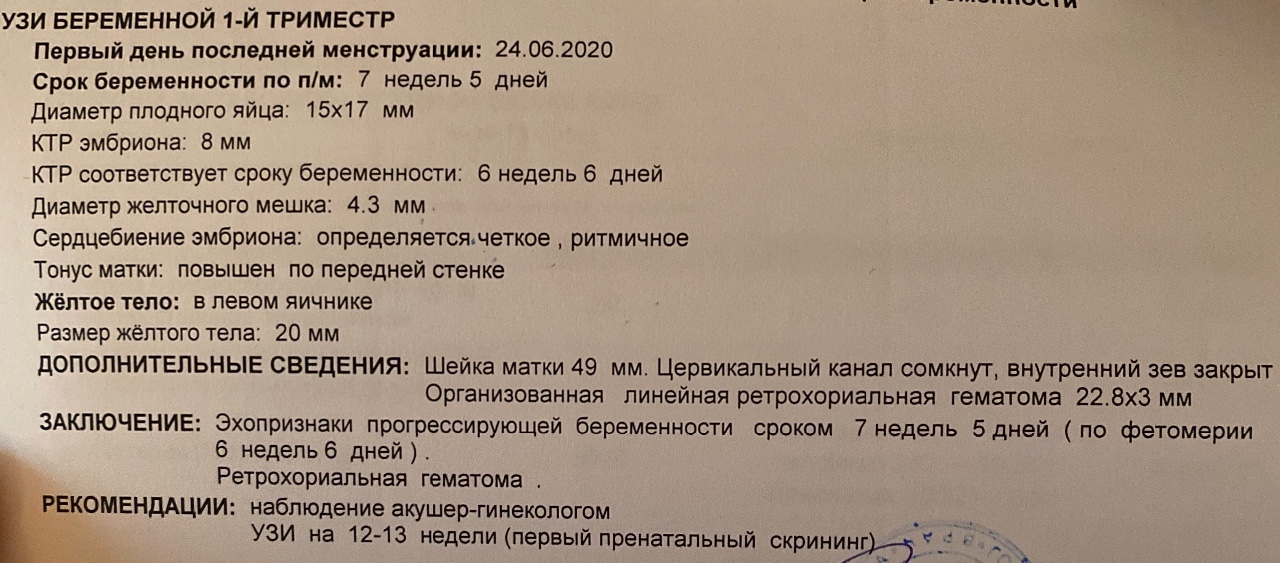

Узи при беременности на раннем сроке.

Информативность узи на ранних сроках беременности

Следите за регулярностью УЗИ, так как мониторинг состояния матки в динамике позволяет выявить возможные отклонения на ранних сроках.